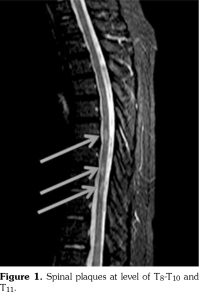

Cranial and spinal magnetic resonance imaging (MRI) showed multiple demyelinating plaques. Thoracal and cranial plaques were not enhancing with contrast agent. Spinal plaques were at the level of T8-T10 and T11 (Figures 1 and 2). Oligoclonal immunoglobulin (Ig) G bands (type II) were detected by immunofixation electrophoresis in cerebrospinal fluid (CSF). Neuromyelitis optica IgG was not found in CSF. Right tibial sensorial evoked potential latency was 64.2 milliseconds and left tibial potential latency was 46.1 milliseconds. He was diagnosed as MS and treated with 1000 mg/daily corticosteroid therapy for seven consecutive days. His hypoesthesia was completely resolved while paraparesis was almost resolved. However, his gait was still ataxic. Interferon (IFN) beta-1a was initiated three times/weekly subcutaneously. On monthly follow-ups, there was no attack for MS. The patient discontinued colchicine treatment by his own will after five months of IFN treatment because he did not suffer from any FMF attacks. He did not suffer even a mild FMF attack from september 2017 until now. He is also under control for MS.